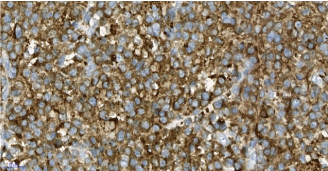

Histopathologic examination of the right lobe showed a 4 cm nodule (Figure 1) and an accompanying papillary cancer on both lobes. The 4 cm nodule consisted of monotonous cells with middle-sized cytoplasm and eccentric nucleus which is may be seen in medullary thyroid cancer and Hurthle cell neoplasms. Amyloid and calcitonin staining were negative. Also, thyroglobulin, TTF-1 and cytokeratin were negative ruling out epithelial thyroid lesions. Immunohistochemistry analysis was positive for CD138, CD38, CD20 with kappa light restriction, but negative for lambda light chains (Figure 2), PAX5 and CD45. Ki-67 showed as low proliferation rate (15%).

Figure 2b. CD38x40

Figure 2c. 2c- CD20 positive cells have plasmacytoid morphology. CD20X40

Figure 2d. Diffuse staining of neoplastic cells with kappa. X40

Figure 2e. Neoplastic cells are negative with lambda; only one plasma cell is positive in this area. X40